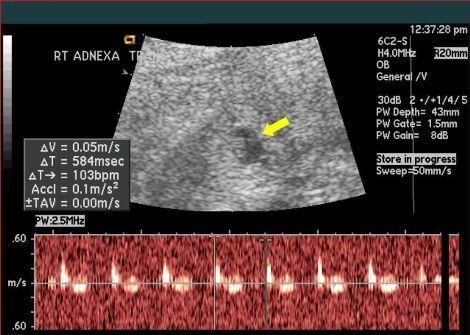

This is a confirmed case of scar ectopic pregnancy. Yesterday, I carried out this exam in an emergency room, without much time to perform an adequate sonogram, the patient did not feel good with “cramps” but no signs of bleeding.